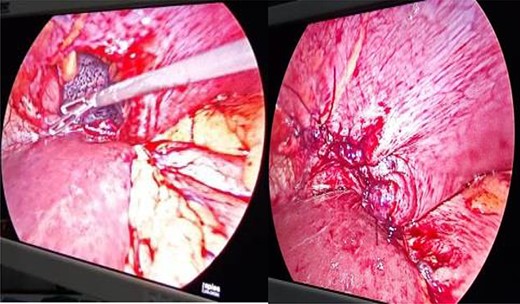

Closed defects were strengthened with mesh (Fig. 5).

Strengthening of defect closure site with composite and polypropylene mesh.